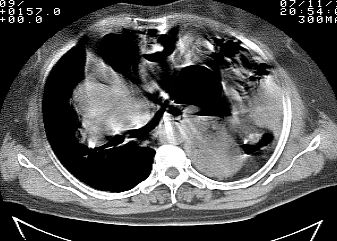

标题: CT10753:女, 64岁 隔疝 [打印本页]

标题: CT10753:女, 64岁 隔疝

女, 64岁 三十年前胸部外伤史, 间断胸闷,

典型左侧膈疝,疝出物为胃和大网膜,纵隔右移

30年了,病人够痛苦的了,应该做修补术。

左侧隔疝(创伤性?),与外伤关系大。